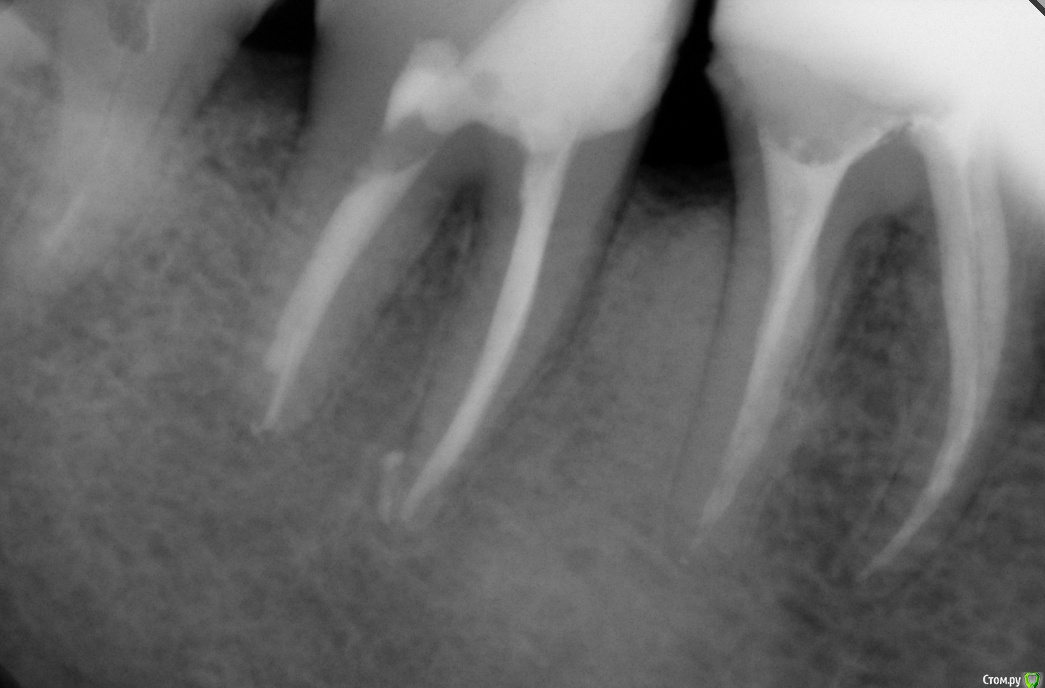

Гарриевич Опубликовано 22 декабря, 2017 Поделиться Опубликовано 22 декабря, 2017 (изменено) админы, если уже создавал такую тему, объедините пожалуйста абсолютно бессимптомный зуб, пациента ничего не беспокоило кроме... да нет, вообще ничего не беспокоило. Лечение в два посещения через гидроксид кальция. Обтурация инжектором. Будут вопросы спрашивайте, каких то еще особенностей сразу не вспомню PS сроки наблюдения 10 месяцев и два года Изменено 22 декабря, 2017 пользователем Гарриевич 8 Ссылка на комментарий

dentikl Опубликовано 23 декабря, 2017 Поделиться Опубликовано 23 декабря, 2017 (изменено) вопрос-1)на фото гутта в проекции фуркации 7 а на рентгене от 26 11.16-в проекции 6. 2)сколько держите под кальием 3)какой кальий используете. спасибо Изменено 23 декабря, 2017 пользователем dentikl Ссылка на комментарий

Гарриевич Опубликовано 23 декабря, 2017 Автор Поделиться Опубликовано 23 декабря, 2017 Скорее всего гутту съехала пока снимки делали. Вложения гидроокиси на 2 недели. В данном случае порошок чистого гидроксида кальция замешанный с водой непосредственно перед внесением. Также испольщую кальцетин технодентовский Ссылка на комментарий